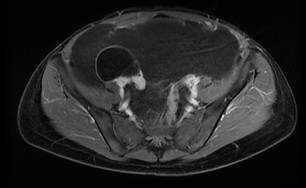

Se realizó una resonancia magnética de abdomen y pelvis que demostró la ocupación de todos los recesos peritoneales con líquido complejo de diferentes captaciones y septos multiloculados, la ocupación del espacio subfrénico derecho debido al desplazamiento tanto del hígado en sentido superior, como de las asas intestinales incluyendo el colon derecho en sentido central y en sentido posterior rechazando el colon descendente. No había compromiso retroperitoneal. Se encontró además una lesión quística dominante adyacente al pedículo ovárico derecho sin conformarse propiamente una masa ovárica, lo que hizo sospechar el origen en la trompa. Debido a la presentación clínica y a los resultados de la resonancia, se sospechó un pseudomixoma peritoneal de probable origen apendicular (Figuras 1,2,3).